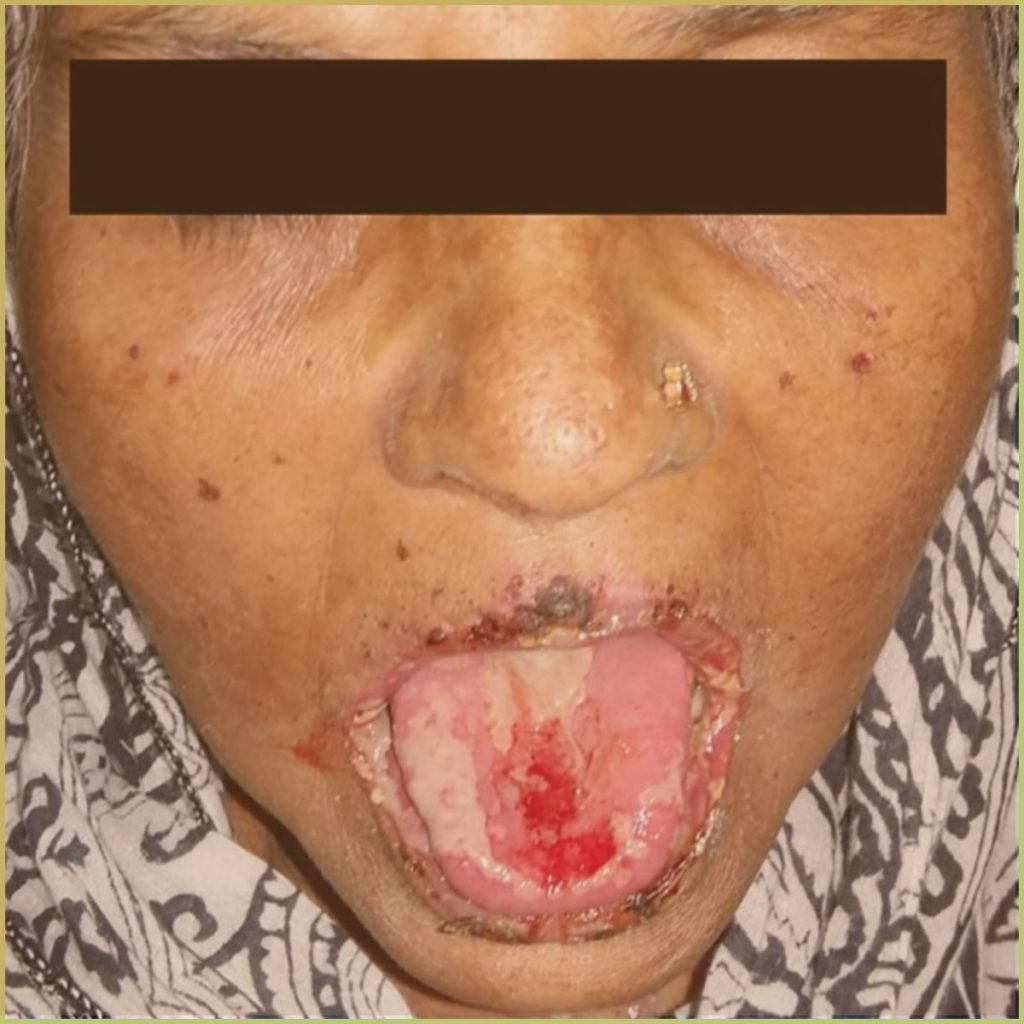

STEVENS-JOHNSON SYNDROME

Stevens-Johnson syndrome is a rare but potentially life-threatening auto-immune disorder (type IV hypersensitivity reaction) that leads to blistering and skin-detachment. Drugs (lamotrigine, carbamazepine, allopurinol, sulfonamide antibiotics, nevirapine) and infection (mycoplasma pneumoniae, cytomegalovirus) are the most likely triggers. Stevens-Johnson syndrome is distinct from and can be confused with Erythema multiforme, but may sometimes be referred to as erythema multiforme major. The common clinical presentation includes:

- Cutaneous appearance of painful erythematous rashes, bullae, and erosions.

- May appear on the face and trunk and may spread to the extremities.

- Labial vermilion and anterior portion of oral cavity usually affected initially.

- Early macular phase followed by erosion, sloughing, and painful ulceration.

- Lip ulcers appear crusted and hemorrhagic.

- Target lesions (Iris lesions) on the skin.

- Several complications associated with the eyes, liver, kidneys, and respiratory tract.

Diagnosis is based on the lesion history, clinical presentation and microscopic findings, which may include:

- Epithelial and connective tissue edema.

- Separation with basal cell liquefaction.

- Intraepithelial neutrophils and perivascular lymphocytic infiltrate.

Your differential diagnosis should include:

- Pemphigus vulgaris.

- Mucous membrane pemphigoid.

- Bullous pemphigoid.

- Acute herpetic gingivostomatitis.

Treatment options include:

- Identification and elimination of predisposing factor(s).

- Topical corticosteroids.

- Systemic corticosteroids (prednisone) or other immunosuppressive medications.

- In the case of a viral trigger, antiviral medications.